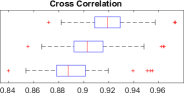

Image Quality Assessments: We compare HR ground-truth 3D volumes with upsampled LR raw data by measuring PSNR, SSIM and cross-correlation. We report SSIM, in particular, due to the well-understood metric properties that afford assessment of local structure correlation and reduced noise sensitivity. LR test imagery is upsampled in-plane () by factors of , to align with target ground-truth resolution. Quality metrics in Fig. 1 report improvements observed for an image upsampling factor of . This provides initial evidence in support of our hypothesis; learning problem and sensor specific deconvolutional filters to perform MRI stack upsampling is of benefit for subsequent resolution-sensitive tasks such as motion compensation and HR volume reconstruction.

By learning problem specific HR synthesis models, our 3D MRI CNN strategy outperforms the naïve baseline up-sampling, quantitatively improving the quality of the inferred HR imagery. Fig. 2 exhibits an example of qualitative improvement in orthogonal fetal MRI test-stack axes.